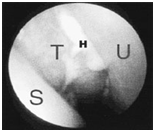

5mm contiguous scan were obtained in the coronal plane without contrast administration

Mucosal thickening was seen in bilateral Maxillary Sinuses, Sphenoid Sinus, frontal and ethmoid sinuses

The nasal turbinates appear normal

Ostia of bilateral maxillary sinuses are patent. Infratemporal fossae are normal on both sides

Nasopharynx appears normal

No bony erosion is seen

Opinion: Pan Chronic Sinusitis

5mm contiguous scans with 3mm reconstruction were obtained in coronal plane without contrast administration.

Nasal Septum S-shaped deviated to right in anterior and left to posterior.

Sphenoid sinus, Left Maxillary Sinus floor, Right Maxillary Sinus Medial roof, Right frontal sinus show lobulated soft tissue densities structure suggestive of polyps.

Bilateral Ethmoid sinus show mucosal thickening suggestive of sinusitis with soft tissue density polyp extending into nasal cavity.

Air fluid levels seen in both maxillary sinuses.

Bilateral osteomeatal units are obliterated.

Infratemporal fossae are normal on both sides.

Nasopharynx appears normal.

Opinion

1. DNS

2. Acute On Chronic Bilateral Ethmomaxillary Sinusitis with Sinonasal Polyposis.